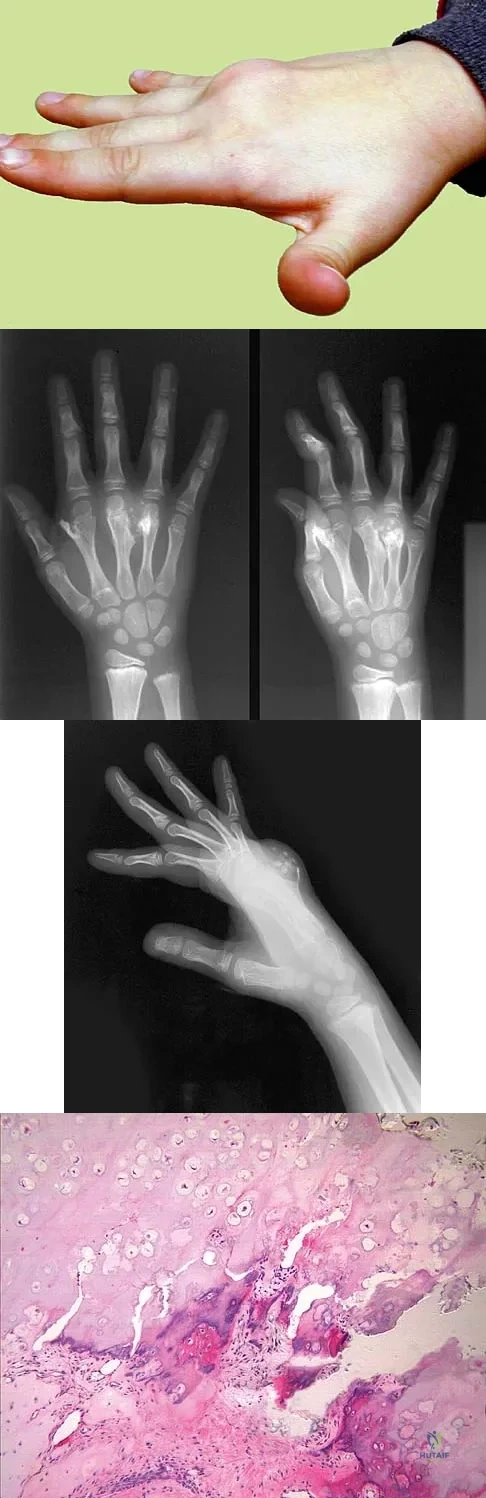

A 9-year-old boy has a painless enlarged mass on the dorsum of his hand. Figures 14a through 14d show the clinical photograph, radiographs, and biopsy specimen. What is the most likely diagnosis?

Explanation